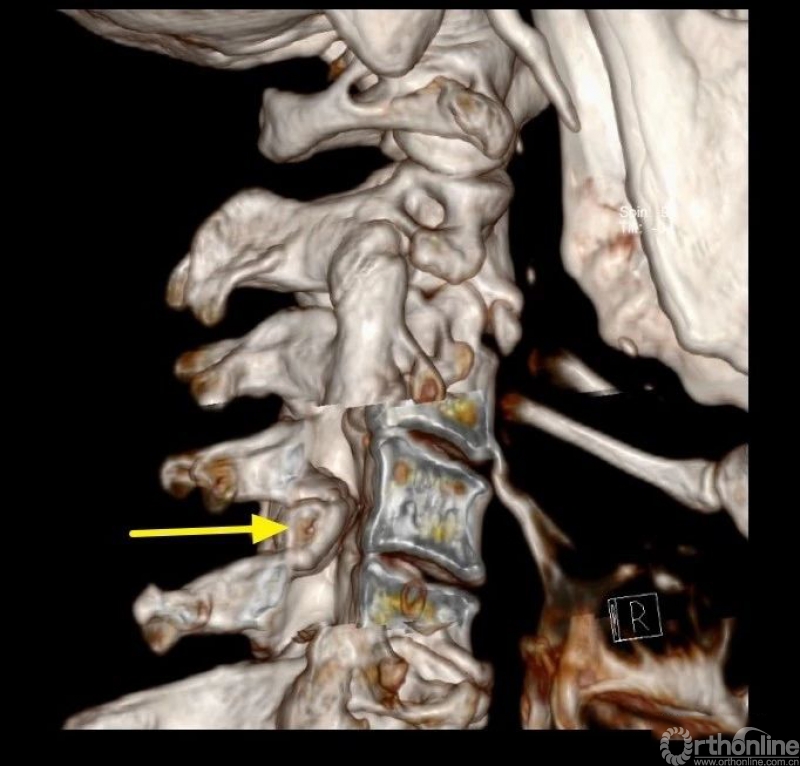

入院查体患者四肢肌张力高,双侧hoffman阳性。CT及MRI检查提示C4/5左侧关节突内缘有一巨大骨块(15mm*16mm),相应节段椎管严重狭窄。椎管内骨块的前端还有一游离骨块。

影像学资料

1.术前评估骨赘侧的椎板间隙几乎完全消失,镜下识别解剖标志困难;